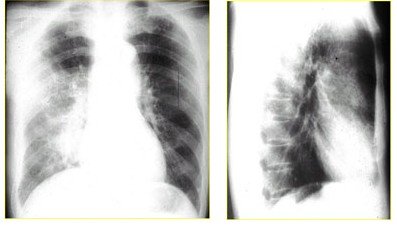

(3)肺脓肿:中毒症状重,大量黄痰,x线阳性

http://webres.medlive.cn/upload/000/062/244